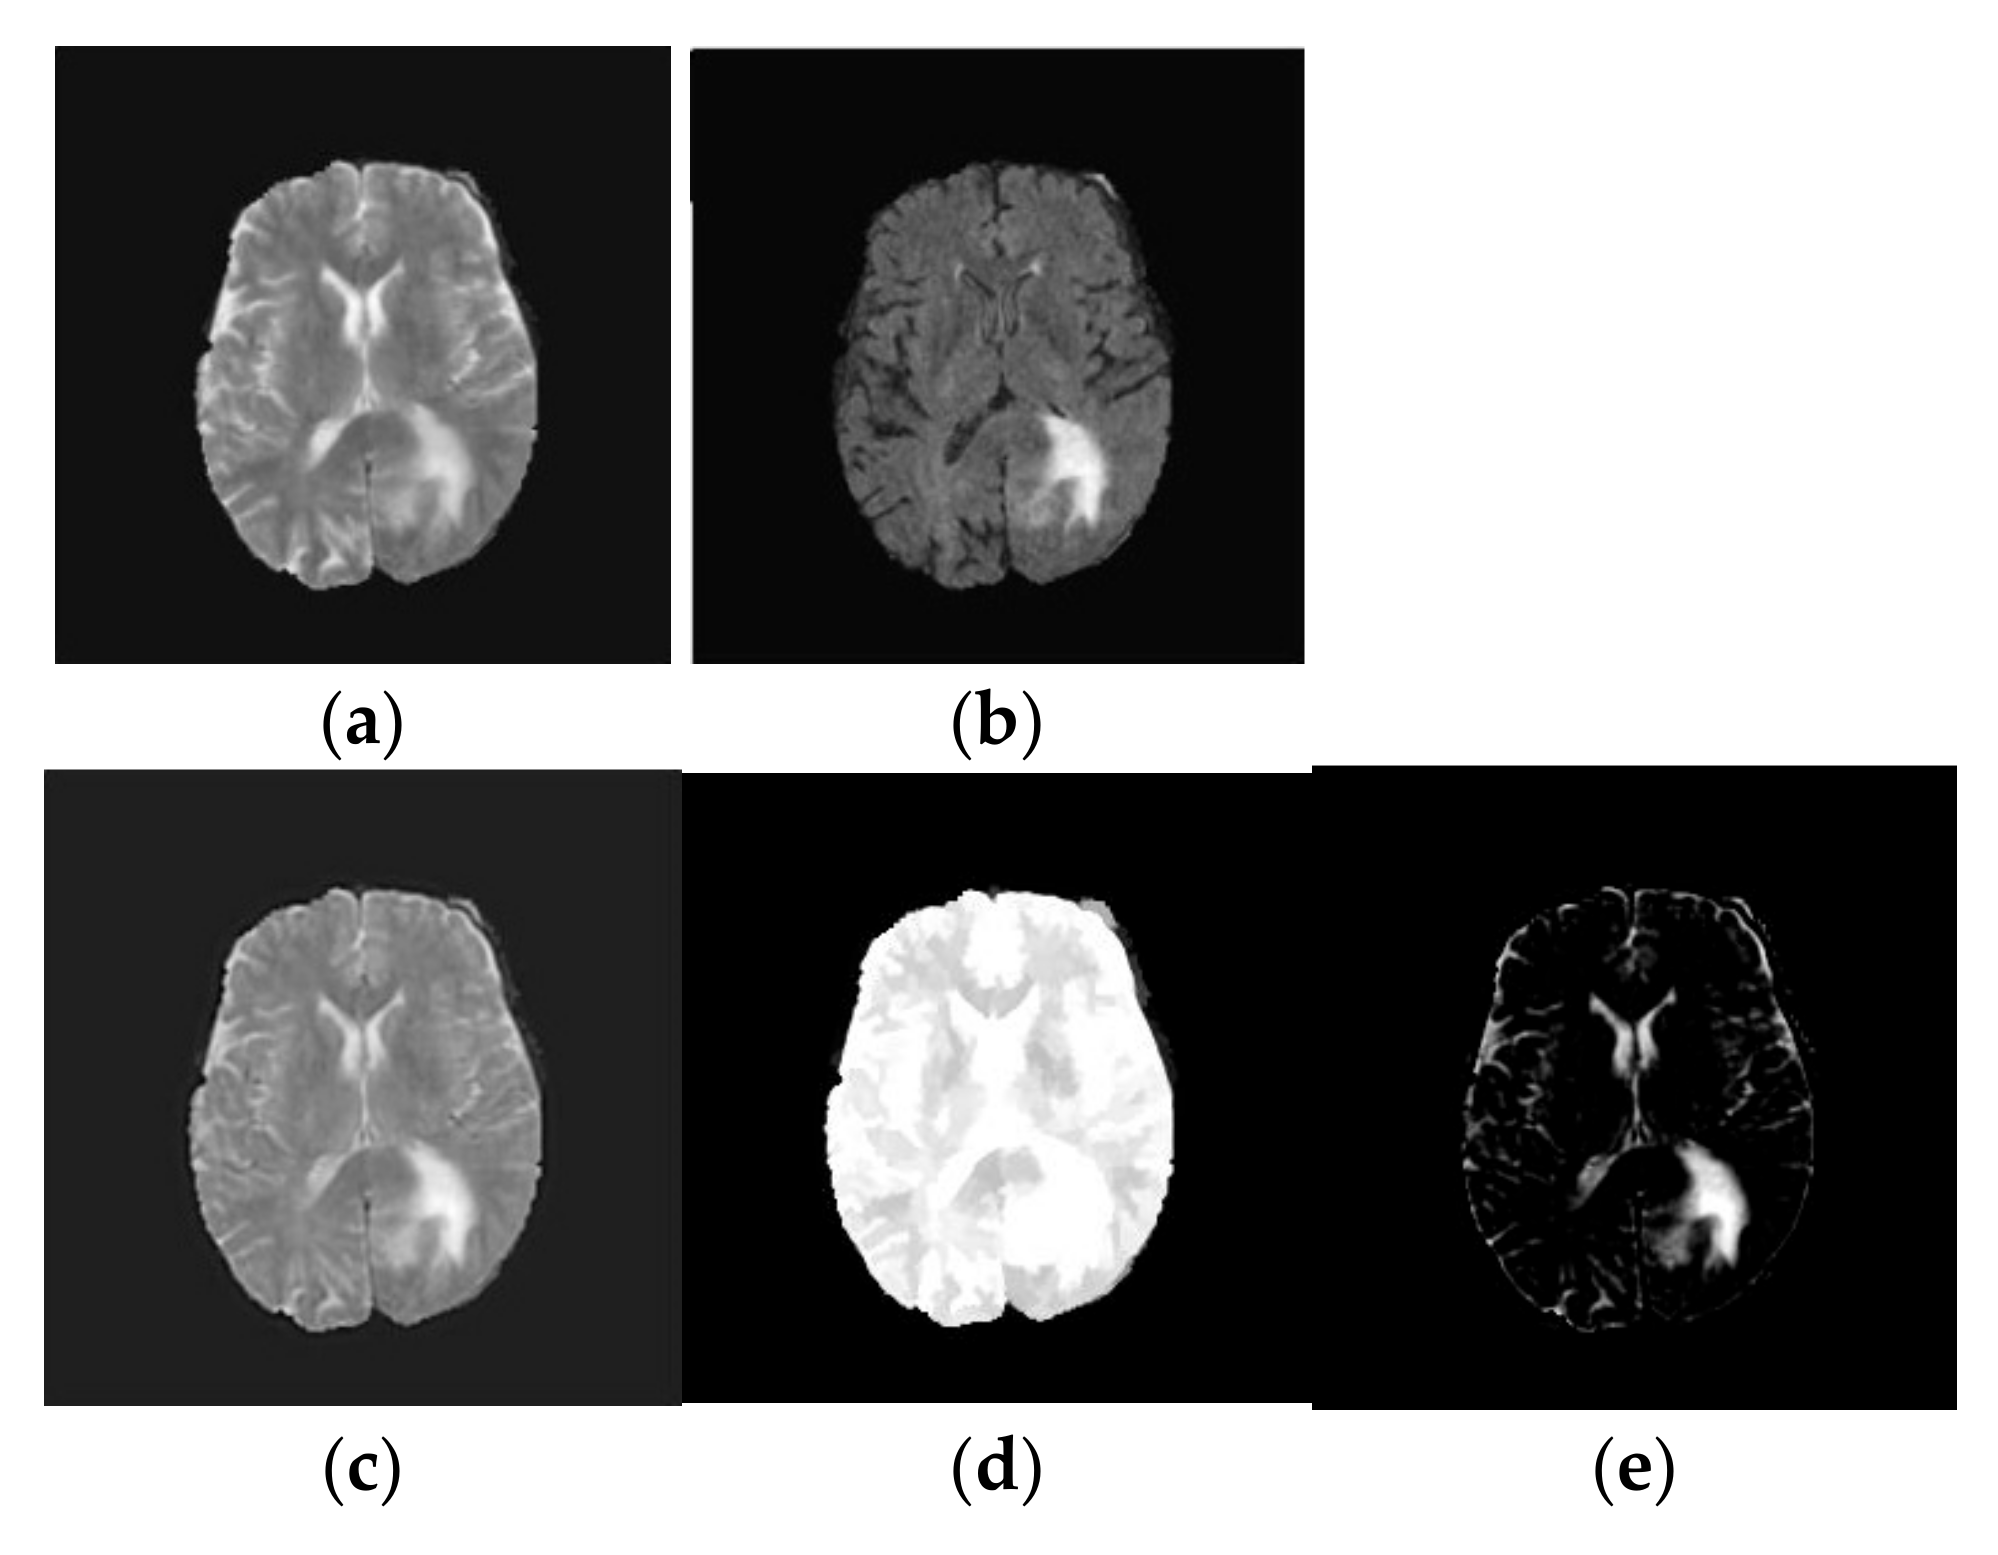

- Image Reconstruction: Finally, the fused low-frequency and high-frequency subbands are recombined using the inverse NSLP. This process reconstructs the final fused MRI image, which is expected to contain the complementary information from both T1-weighted and FLAIR images. The implications of the fused process are shown in Figure 3.

- TV-L1 Decomposition: The primary objective of our method is to decompose the fused image, into two distinct components: a piecewise smooth (geometric) component and a texture component. The geometric component represents the smooth regions and boundaries of the image, while the texture component captures oscillating features, including edges and noise. In medical imaging, the texture component often contains critical structural details that are essential for tasks such as tumor classification. These structural details can be effectively extracted using the TV-L1-based cartoon-texture decomposition technique. The TV-L1 method separates the fused brain MRI tumor image into two components: the cartoon (geometric) component and the texture component, as outlined in [18]:where gives the cartoon part and which characterizes the geometric component of the fused image. Similarly, represents the texture part of the fused image. The cartoon component of the fused image is attained by minimizing the following objective function [18]:where represents the gradient operator and λ defines the regularization criteria which is a trade-off between the fidelity criteria and regularization term. In this work, we chose λ as 0.1. Similarly, denotes the image domain and the symbol represents L1 normalization. The first part of Equation (2) represents the TV of cartoon component and the second part specifies the fidelity to make the cartoon part keep close to the fused image, and they are calculated over the image domain Ω. The solution to Equation (2) is resolved by the following optimization [19]:where and represent the forward and backward differences. provides the magnitude of gradient. The parameter l provides the iteration index. In this, we chose l as 50. is defined as changes in time, and and indicate discrete spatial distances of the image grid. φ and ε (0.00001) are constants. The resultant outcome of TV-L1 decomposition is shown in Figure 3.